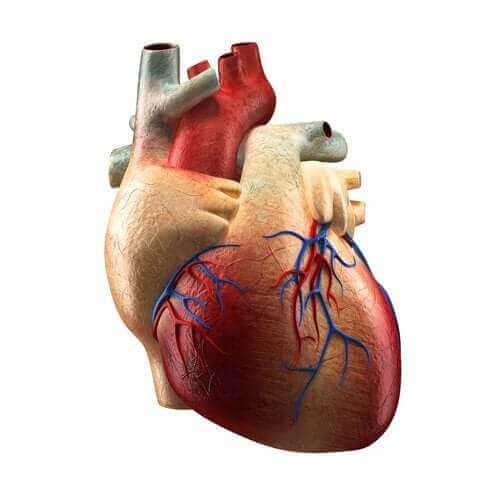

Анатомія та фізіологія

Занурення в людську анатомію та фізіологію допоможе вам зрозуміти, як працює ваше тіло. Ви дізнаєтеся таємниці кожної системи та кожного органу у вашому тілі, знатимете тканини і функції вашого організму, порушення в його роботі, і, найголовніше, як поліпшити ваше здоров'я - і життя.